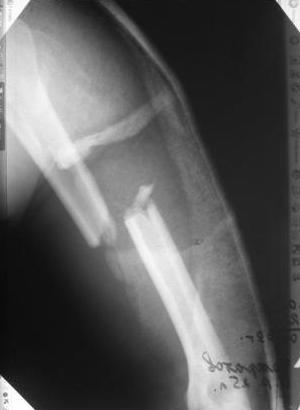

Спасибо Алексей! Я и планировал провести антеградное штифтование но меня смущал относительно небольшой дистальный отломок. Может для кого-то данные вопросы и кажутся пустяком...но я только недавно начал использовать в своей работе штифты преимущественно Synthes. Еще раз спасибо

Давайте я Вам задам несколько вопросов. Какой гвоздь будуете использовать - производитель, длина, диаметр? Будете ли рассверливать канал? Чем, до какого диаметра? Как будете делать репозицию - на руках, дистрактор? Как будете запирать стержень в дистальном отломке - направление, количество винтов?

Всё правильно, просто я несколько разрозненно пытался сказать на частных примерах, то , что Вы систематизировали. Совершенно верно данный перелом можно и так и эдак, наиболее оптимально антеградное штифтование, хотя я бы предпочёл пластину LCP(просто - ну лучше у меня это получается и всё, а больному не вредит тот же функциональный способ). А низковато для неблокированного штифтования с конструкциями с термомеханической памятью, то, что представленно на втором снимке.

По поводу представленного больного, соглашусь, что в дистальном отломке вполне уместится штифт-эксперт, хотя чтобы провести репозицию + заблокировать все 4 отверстия, придется здорово помять окружающие кость ткани.